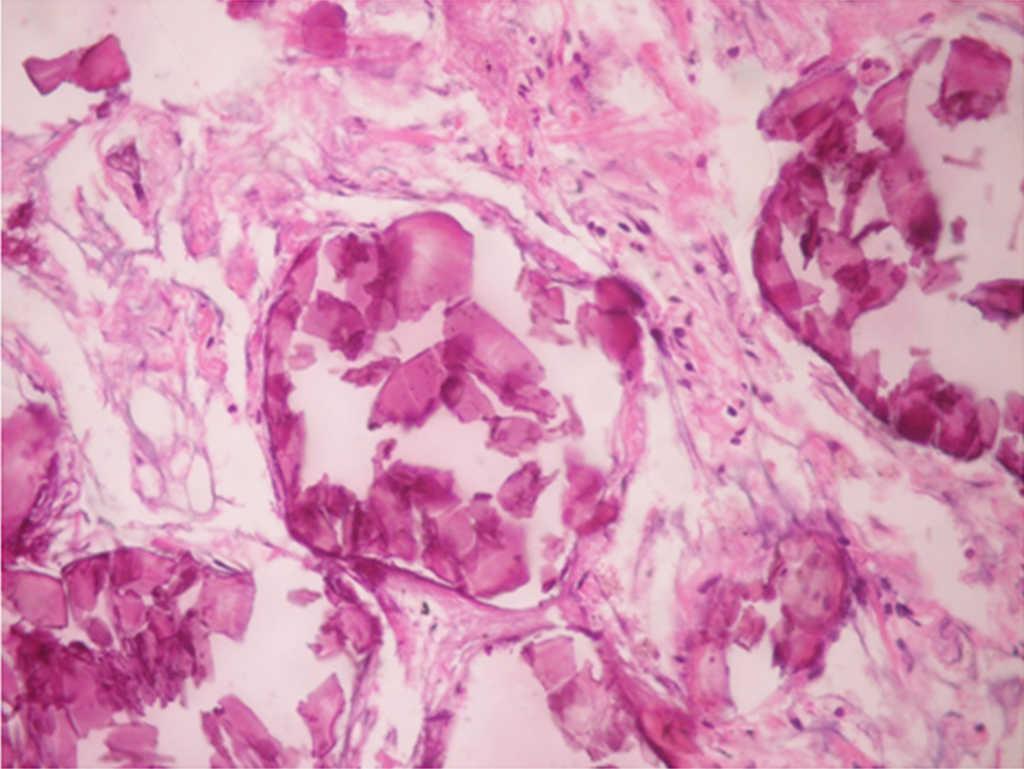

Microlitos alveolares.

Figura 3.

(0,25MB).

Presencia de cuerpos esféricos calcificados (calcosferitas).

Figura 4.

(0,21MB).

En los hallazgos histopatológicos, se encuentran numerosas calcosferitas laminadas, escasa fibrosis de las paredes alveolares y presencia de macrófagos cargados de hemosiderina. Siendo este el reporte de un gran número de casos. El parénquima pulmonar, en la medida que progresa la enfermedad, se degenera causando bulas y fibrosis intersticial. Se describen casos en los que las calcosferitas comprometen las paredes septales, no solo a nivel del espacio alveolar, sino también a nivel bronquial3,22.

Cuando los microlitos se analizan, se observan de forma irregular, redondeados y en ocasiones ovalados, compuestos de láminas con medidas que pueden variar de 0,01 a 0,3mm55, que parecen aumentar en tamaño con la edad hasta ocupar todo el espacio alveolar60 y en estados avanzados entran en contacto con la paredes, dañándolas y siendo estas reemplazadas por tejido fibroso. Los microlitos son compuestos de calcio, fósforo, con concentraciones bajas de hierro, cinc, aluminio y magnesio1,22,61. Su ubicación se da en principio en los lóbulos inferiores, con el trascurrir del tiempo (20 a 30 años), se extienden a todo el pulmón.